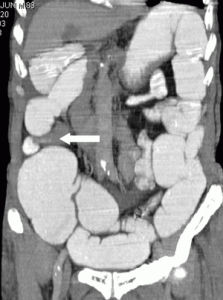

不完全性腸梗阻

腸內容物在腸道中通過受阻,稱為“腸梗阻”。不完全性腸梗阻是指腸道還沒有被完全阻塞,仍有部分食物、水、氣體通過。

完全性腸梗阻表現為嚴重的腹疼、嘔吐、腹脹、肛門排氣排便停止,如不及時治療死亡率很高。不完全性腸梗阻較之完全性腸梗阻症狀較輕。